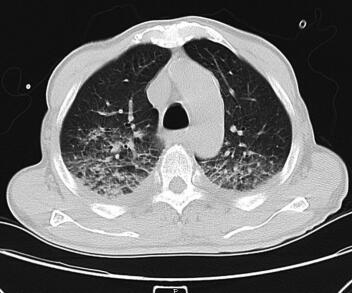

诊治经过:入院后予以吸氧、强心、利尿、抗感染、解痉、平喘、化痰、抗血小板、稳定斑块、营养心肌及改善心肌供血等相应治疗,并给予胺碘酮控制心室率,心室率控制在75~120次/分,气促、胸闷症状得到明显缓解,各项生命体征逐步正常稳定,肺部干湿性啰音逐步减少消失。心脏彩超:左右心房及左心室扩大;左心室弥漫性收缩功能减低;少量二、三尖瓣反流;主动脉瓣退行性变并少量反流;主动脉硬化。肺部CT(图2):双肺纹理增粗、模糊,双肺背侧见大片斑片状渗出及实变影;气道大致通畅,肺门未见明显增大,纵隔内见多发肿大淋巴结。两侧胸腔积液(图1、图3),两下肺膨胀不全。冠状动脉见条形致密影。查血PCT高达84.14ng/ml,入院初始予以头孢哌酮-舒巴坦钠抗感染,PCT逐渐下降,但仍有反复寒战、发热症状,体温波动在37~38℃。直至第4天血培养结果提示金黄色葡萄球菌MRSA(+)。依据药敏试验结果改用环丙沙星和盐酸米诺环素,连续用3天,患者仍有发热、寒战,体温依然波动在37~38℃。遂停用环丙沙星,加用替考拉宁,此后,患者体温明显下降并很快降至正常范围,发热、寒战等症状亦消失。最终病情好转稳定出院。

图2 肺部CT:双肺纹理增粗、模糊,双肺背侧见大片斑片状渗出及实变影